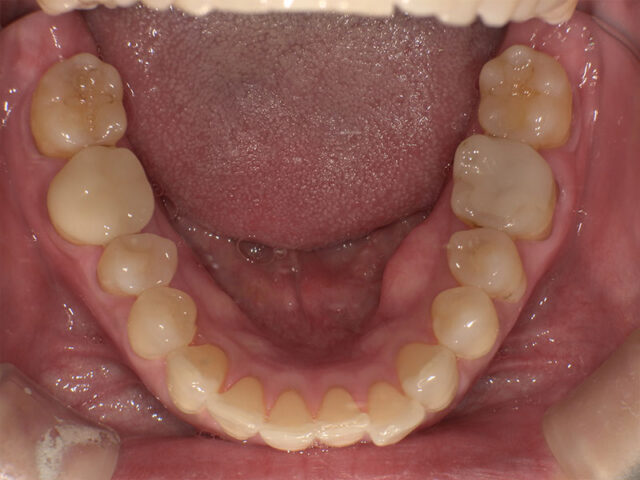

Before

After

| 通院回数 | 12回(治療期間1年) |

|---|---|

| 通院目的 | 歯の移植の相談をしたい |

| 処置内容 | 歯牙移植 |

| 費用 | 移植 15万 根管治療 6万 コア 1万 セレッククラウン 7万 |

| デメリット・注意点 | 生着を必ずするとは限らない 外部吸収のリスクがある 咬合時の違和感が生じる場合がある 失敗した場合には、インプラントを行うに際して骨造成を必要とする。 インプラント治療に比べ、予後が不明確 |